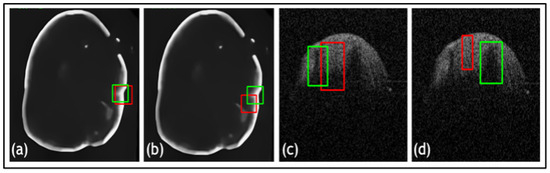

- In TED, the transformer is adapted to take in images and slide across Regions of Interest (ROIs) provided by AGs. This design aims to adaptively deal with different types of noise artifacts and thus effectively detect a variety of anomalies including tooth decay and numerous lesions across two modalities.

- A new loss function is proposed along with TED, which combines a sliding box, Intersection Over Union (IOU), and Mean Squared Error (MSE). It compares the IOU and MSE between the predicted and real bounding boxes to evaluate the regions of focus chosen by the AGs.